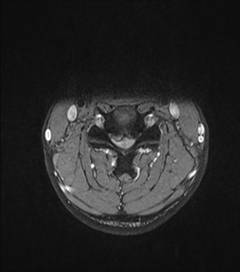

典型病例匯報1:中年男性41歲,因“行走不便2年,加重伴雙手麻木2周”之主訴入院,癥狀主要為:頸部疼痛、僵硬,雙下肢無力、行走不穩(wěn),雙手麻木,協(xié)調(diào)性差,右手握筆困難。入院查體:步態(tài)不穩(wěn),C3-C7壓痛、叩擊痛,肢痛溫覺減退,雙上肢肢肌力5-級,雙下肢肌力4-級,肌張力增高,雙下肢腱反射亢進,病理征(+),行頸前路小切口突出椎間盤切除、前路頸椎橋形鎖定植骨融合(ROI-C假體),無需前路鋼板,術(shù)后四肢麻木明顯緩解,右上肢精細動作明確增強,可寫字,行走不穩(wěn)消失,肌力基本正常,頸部活動度無明顯受限。(1、圖2)

圖1 術(shù)前頸椎MRI提示頸椎退行性變,C4/5椎間盤突出、脊髓出現(xiàn)高信號改變,C4硬膜囊受壓變形